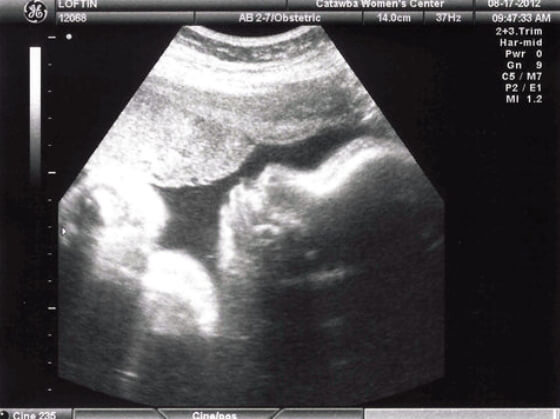

36 Haftalık Bebeğin Ultrason Görüntüsü

Bebeğinizin ultrason görüntüsün, diğer annelerinkinden ve internette karşılaştığınız fotoğraflardan farklı olması gayet doğaldır; çünkü özellikle hamileliğin son dönemlerinde, bebeklerin anne karnındaki duruşu farklılık gösterebilmektedir.

• 36 haftalık ultrason görüntünüzde bebeğinizi çok daha tombul ve yuvarlak yüzlü bir bebek olarak göreceksiniz.

• Bebeğiniz şu an muhtemelen parmaklarını emiyor, ayaklarına uzanmaya çalışıyor ya da hıçkırıyordur; kısacası yenidoğan bir bebeğin hal ve hareketlerini yapıyordur.

• Bu haftaki ultrason görüntünüzde, bebeğinizi baş aşağı dönmüş ve hatta yüzü ters dönük görmeniz mümkündür. Bebeğinizin yüzünün ters olması sizi endişelendirmemelidir; çünkü bu duruş sezaryen doğumu dahi kolaylaştırmaktadır.

• 36 hafta gebelik döneminde bebeğiniz henüz baş aşağı dönmediyse ve doğum pozisyonu almadıysa bile, 38. haftaya kadar vakti olduğunu ve bebeklerin %95’inin doğuma kadar pozisyonlarını ayarladığını belirtmek isteriz. Bebeğiniz şimdilik kendini en rahat hissettiği pozisyonda kalmaya devam ediyor olabilir.